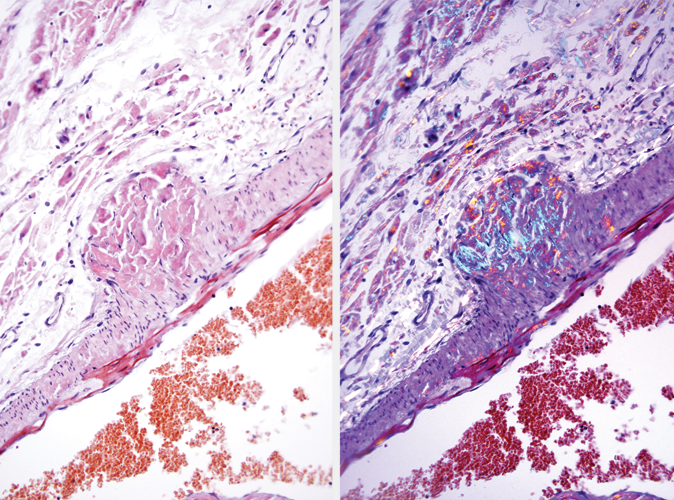

Congo Red, Amyloid Special Stain Kit

The Congo Red, Amyloid Stain Kit